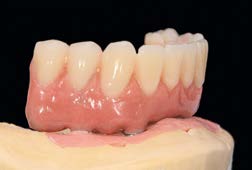

Các Implant ngắn 6.5mm BTI được đặt bằng cách sử dụng quy trình khoan định hướng sinh học (biologically guided drilling protocol) độc quyền của BTI, với lực vặn chèn được đo tại thời điểm đặt để xác nhận sự phù hợp cho việc chịu lực tức thì. Các phục hình tạm thời liên kết bắt vít được gắn ngay sau phẫu thuật để ổn định sự phân bố lực trong quá trình tích hợp xương. Từ 3 đến 6 tháng sau, chúng sẽ được thay thế bằng các cầu răng sứ kim loại cố định hoặc phục hình lai kim loại-nhựa, đảm bảo phục hình hoàn hảo cho bệnh nhân tiêu xương dọc.

Về phương diện chức năng, không có Implant ngắn 6.5mm BTI nào mất sự ổn định lâm sàng hoặc có dấu hiệu X-quang về các biến chứng cơ sinh học trong thời gian theo dõi 8 năm. Phục hình tạm và phục hình vĩnh viễn trên nền tảng tiêu xương dọc đều duy trì sự ổn định tối ưu. Không ghi nhận bất kỳ các biến chứng cơ học đáng kể hay sự cố viêm quanh Implant.

Mức tiêu xương viền trung bình ở lần theo dõi cuối là 0.52 ± 0.41mm (phía gần) và 0.47 ± 0.38mm (phía xa). Tỷ lệ sống sót tích lũy đạt 100% cho Implant ngắn 6.5mm BTI.